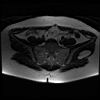

bekken